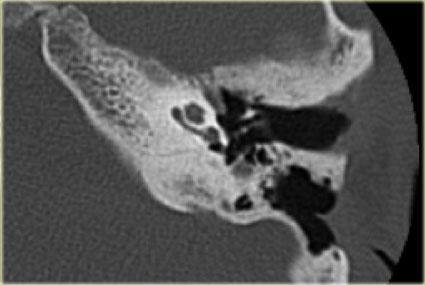

U túi nội dịch (ELST): quá trình phá hủy xương thái dương mặt lưng, kèm vôi hóa (mũi tên). Vị trí, mức độ phá hủy và vôi hóa là những đặc điểm điển hình của ELST. Có một phần nhỏ khối u lan vào tai giữa

U túi nội dịch (EndoLymphatic Sac Tumor – ELST)

ELST là một thực thể bệnh lý hiếm gặp.

Các khối u này xuất phát từ túi nội dịch.

Chúng tôi đề cập đến loại u này vì hình ảnh CT của chúng rất điển hình.

Trên CT, có thể thấy quá trình phá hủy xương ở mặt lưng phần đá của xương thái dương kèm theo các vôi hóa dạng chấm.

Trên MRI, thường có ngấm thuốc tương phản từ mạnh.

Mức độ phá hủy xương trong trường hợp này sẽ không điển hình cho u màng não (meningioma).

Hình bên trái cho thấy một quá trình phá hủy xương lớn ở mặt lưng xương thái dương.

Một phần khối u ngấm thuốc tương phản từ mạnh.

Có một thành phần dạng nang ở mặt lưng không ngấm thuốc.

Lưu ý thành phần dạng nang của khối u trên hình ảnh chuỗi xung T2W